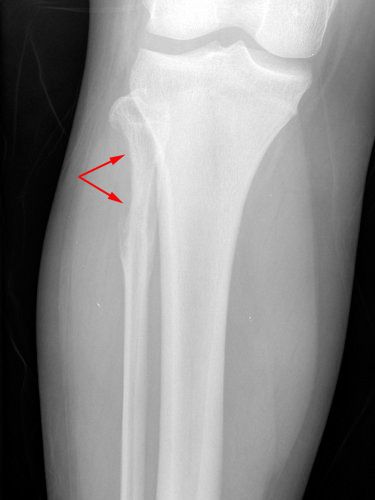

5. Ewing’s Sarcoma

- Number of People Afflicted Yearly: 3 per 1 million people

- Area of Body Affected: Bone or soft tissue of the pelvis, the femur (thigh bone), the humerus (upper arm bone), the ribs, the mandible (jaw), or the clavicle (collar bone)

- Is it Treatable?: Yes

- Survival Rate: 5-year survival rate for localized tumors is about 70% and 30% for metastatic tumors

Ewing’s sarcoma is an exceedingly uncommon kind of cancer that typically strikes young people under the age of 20.

This includes children, teenagers, and adults. In 1921, American doctor James Ewing was the first person to describe this particularly aggressive form of bone cancer.

Ewing’s studies demonstrated that it was a unique form of cancer that was distinct from both lymphoma and neuroblastoma. This was despite the fact that similar forms of tumors had been identified roughly a century before.

The majority of people diagnosed with Ewing’s Sarcoma are between the ages of 10 and 20, making those diagnosed with the disease after the age of 25 an exceptionally unusual occurrence.

According to the findings of several studies, males and young men have a higher risk of developing Ewing’s Sarcoma compared to girls.

When it comes to localized tumors, the 5-year survival rate for Ewing’s Sarcoma is relatively high. In general, roughly 70 percent of people diagnosed with Ewing’s Sarcoma live beyond five years after their diagnosis.